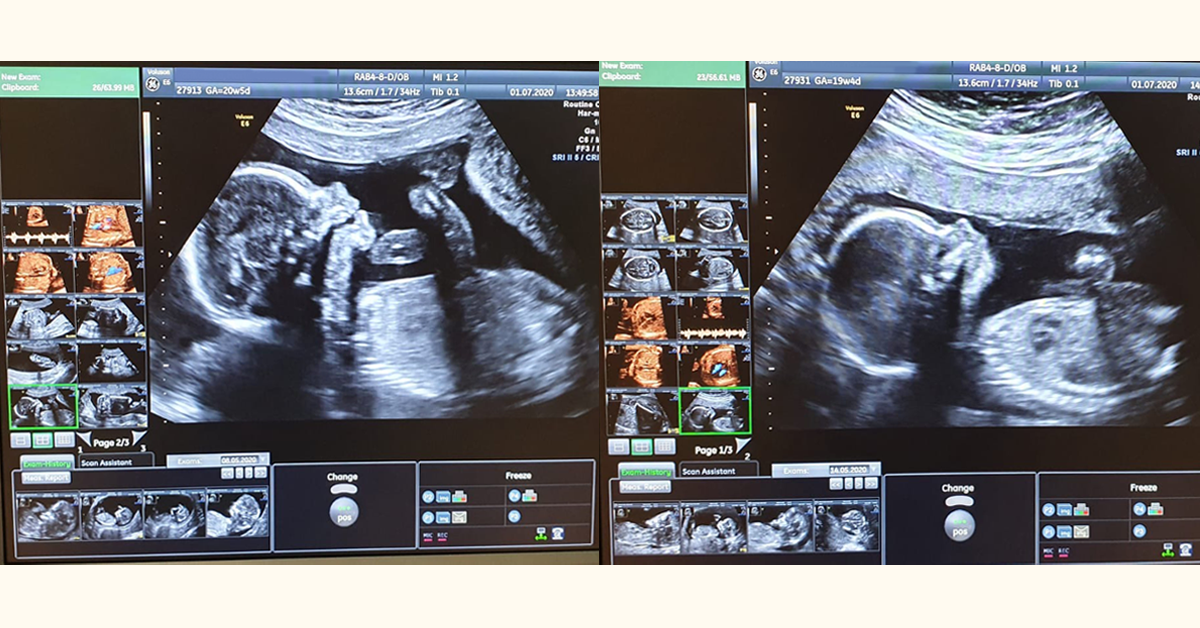

USG genetyczne: Nie tylko bicie serca, czyli co lekarz widzi na ekranie

Podczas USG genetycznego, wykonywanego przez doświadczonego specjalistę, lekarz nie tylko upewnia się, że serce dziecka bije prawidłowo, ale przede wszystkim dokładnie ocenia szereg markerów ryzyka wad genetycznych. To bardzo szczegółowe badanie, które wymaga precyzji i wprawy. Oto kluczowe elementy, które są sprawdzane: